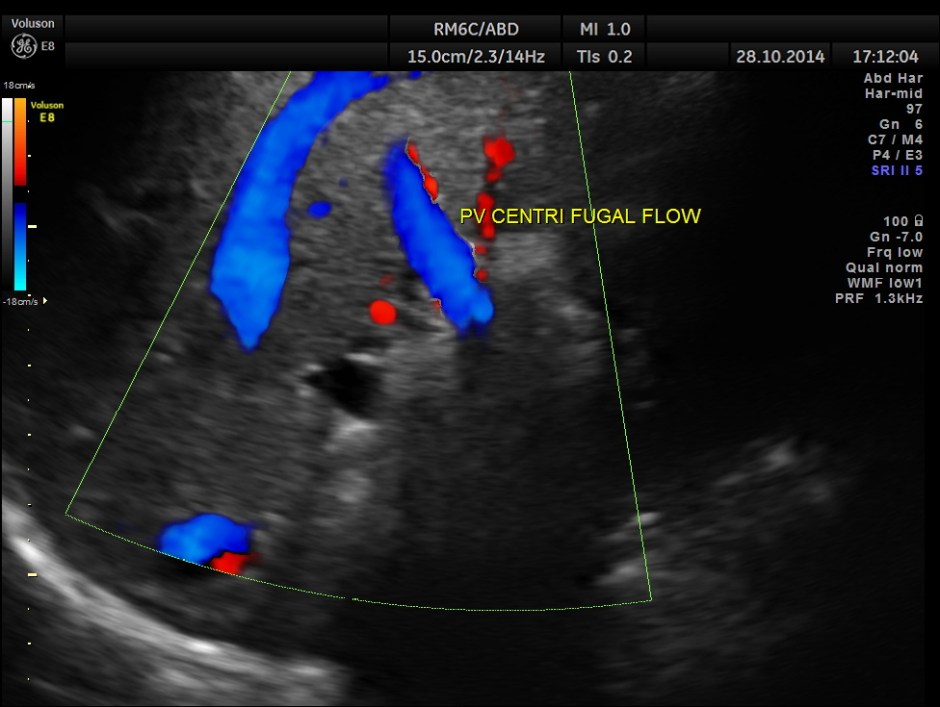

Main portal vein show flow reversal ( blue colour ) – centri-fugal flow suggestive of portal hypertension.

This patient has cirrhosis of liver with portal hypertension – flow reversal of main portal vein , splenomegaly , mildly dilated splenic vein and varices around the gallbladder.